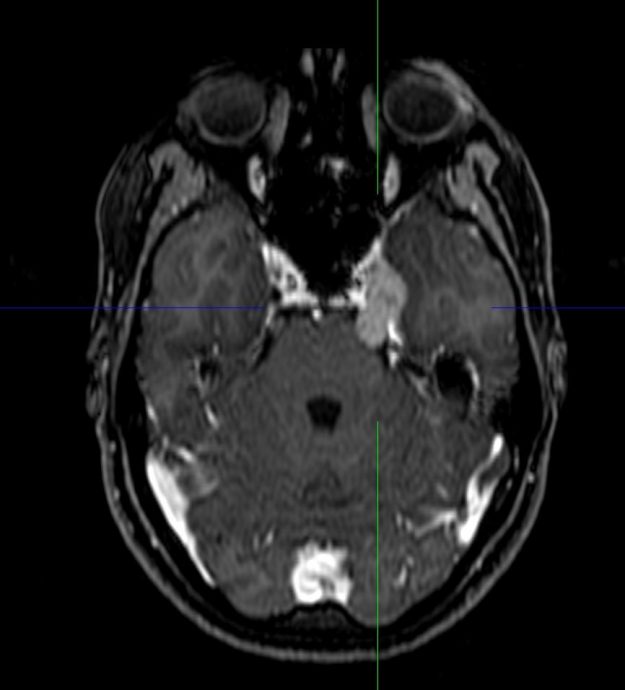

Αραχνοειδής Κύστη Εγκεφάλου

Ασθενής γυναίκα 58 ετών με πονοκεφάλους και διαταραχές όρασης. Ο οφθαλμολογικός έλεγχος έδειξε οίδημα οπτικών θηλών άμφω και σημαντικό περιορισμό των οπτικών πεδίων. Τα συμπτώματα της ασθενούς ήταν προοδευτικά επιδεινούμενα, το ίδιο και οι εξετάσεις της. Η μαγνητική εγκεφάλου ανέδειξε ευμεγέθη αραχνοειδή κύστη δεξιά κροταφικά με σημαντική πίεση επί του υγιούς εγκεφάλου και παρεκτόπιση των…